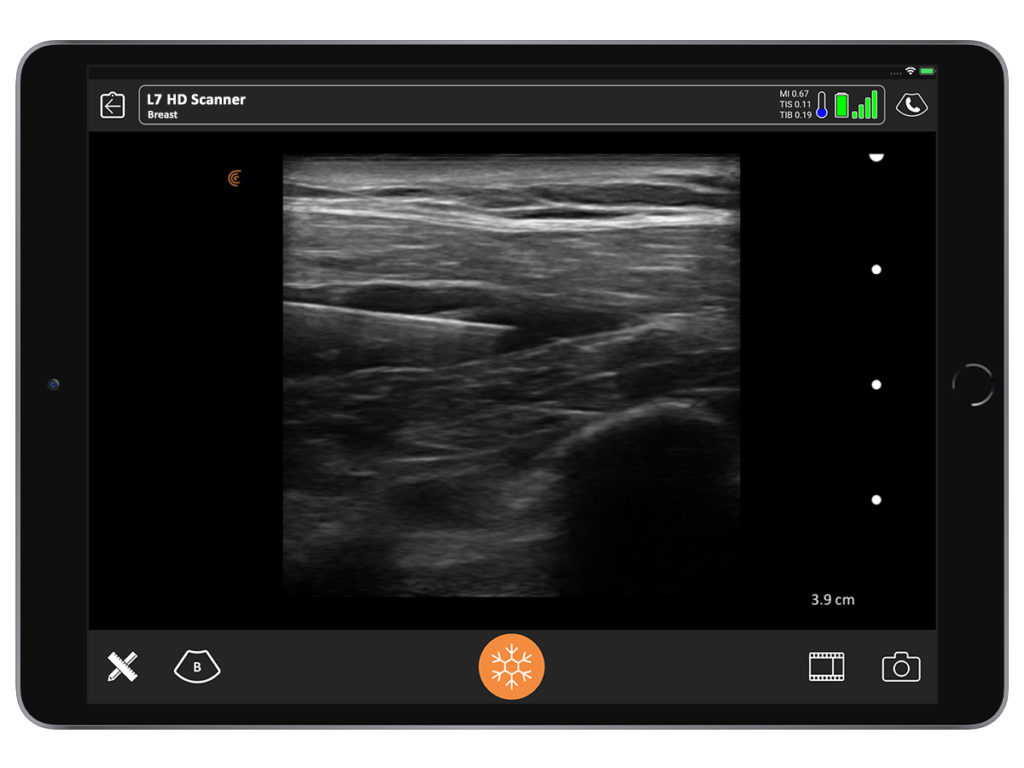

I use ultrasound for many applications in my practice. For breast, it enables me to make the diagnosis in just one patient visit. By looking under the skin, I can quickly answer several questions without sending the patient to a radiologist.

If an aspiration is needed, for example, I can do it in the office instead of waiting for someone else to do it. By using ultrasound, I’m able to say with a good degree of certainty whether an implant is broken or not. I’ve never seen a false negative.

With ultrasound, you can tell a saline implant from a gel implant. You’re also able to differentiate between a textured versus a smooth implant. It’s also very easy to see a seroma. So, if you detect a smooth implant and the absence of seroma, you can tell your patient she’s unlikely to have ALCL.